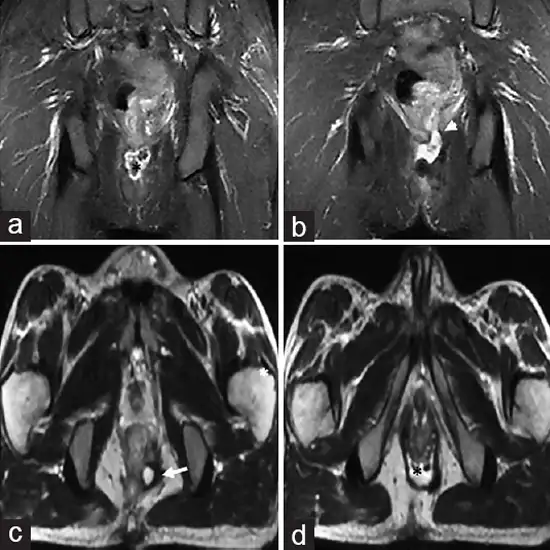

An MRI Fistulogram test is an imaging technique performed on the patients undergoing surgery related to anal, anovaginal, or rectovaginal fitulus issues.

The MRI Fistulogram test is necessary to scan and detect the present situation of your anal fistula. It even helps to determine the associated abseccess along with the appropriate surgery required as per the seriousness of the issue.

An MRI fistulogram is the magnetic resonance imaging of the anatomical structures like the anus, vagina, rectum, etc. The imaging results of these structures can help determine associated infections and diseases.

The MRI fistulogram is used to visualise anatomical fistulas present in the body for any abscess, infection, or other abnormalities. The MRI images of fistulas can help in evaluating the seriousness of the underlying organ and its tissue.

The MR fistulogram is quite sensitive and accurate in diagnosing  infections and abnrmalities associated with the natural fistulas. It has a sensitivity of 90.5%, a specificity of 100% and an accuracy of 97%.